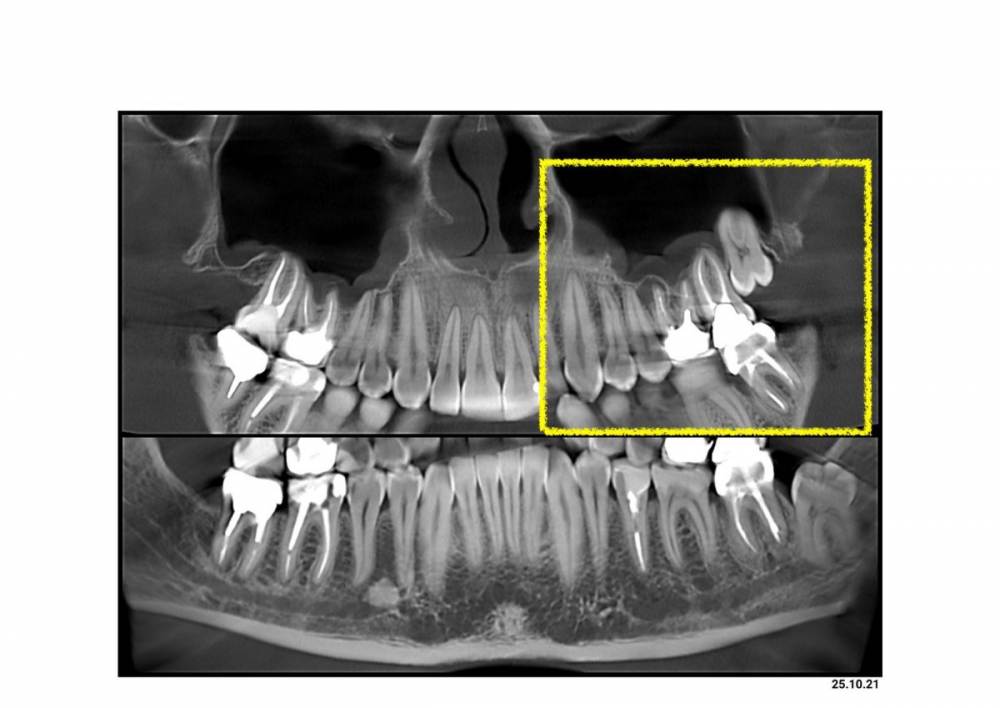

Complient Опубликовано 16 ноября, 2021 Поделиться Опубликовано 16 ноября, 2021 (изменено) Добрый день, буду признателен за мнения на мой случай. Ситуация: - на корне 6-го (под коронкой) воспаление (видно на фото КТ снимка) - на 7-м под вкладкой оказались сильные разрушения (видно на фото) Предлагают удалить 26,27,28 разом, чтобы потом, как заживет, ставить 2 импланта. Интересует мнение сообщества: 1) Есть ли риски удалять 8-ку сразу вместе с 6 и 7? Или лучше позже отдельно? 2) Нужен ли тут синус-лифтинг? 3) Через сколько после удаления можно приступать к имплантам/синус-лифтингу? Изменено 16 ноября, 2021 пользователем Complient Ссылка на комментарий

Женька Опубликовано 16 ноября, 2021 Поделиться Опубликовано 16 ноября, 2021 Здравствуйте. Если любите удалять зубы то можете хоть каждый зуб из представленных отдельно удалять Синус скорее всего нужен будет, но по представленному срезу сказать об этом точно нельзя 1 Ссылка на комментарий

Irouil Опубликовано 16 ноября, 2021 Поделиться Опубликовано 16 ноября, 2021 Удалять лучше вместе Чтобы оценить перспективы имплантации и синус-лифта нужно КТ 1 Ссылка на комментарий

Complient Опубликовано 17 ноября, 2021 Автор Поделиться Опубликовано 17 ноября, 2021 22 часа назад, Женька сказал: Здравствуйте. Если любите удалять зубы то можете хоть каждый зуб из представленных отдельно удалять Синус скорее всего нужен будет, но по представленному срезу сказать об этом точно нельзя 22 часа назад, Irouil сказал: Удалять лучше вместе Чтобы оценить перспективы имплантации и синус-лифта нужно КТ Спасибо! Услышал, что все сразу лучше и рисков от этого не больше. Ссылка на комментарий